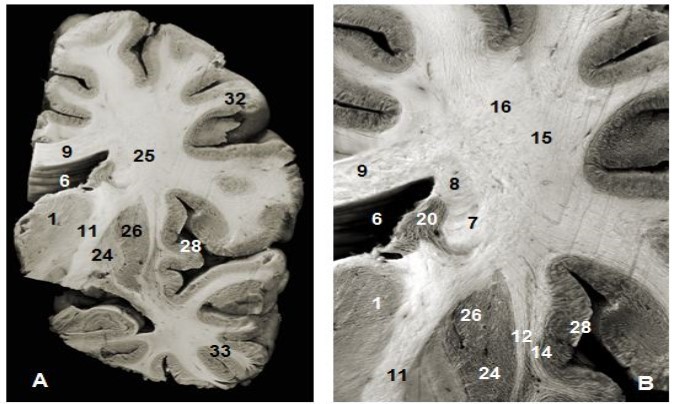

Figure 1.(A) Coronal view of the left hemisphere and (B) global view after magnification and before dissection of (A). 1. Thalamus, 6. Lateral ventricule 7. Subependymal substratum, 9. Corpus callosum, 11. Internal capsule, 12. External capsule, 13. Claustrum, 14. Extreme capsule, 16. Upper branch of the SLF , 20. Head of caudeus nucleus, 23. Putamen, 24. Globus pallidus, 25. Lower branch of SLF 28. Insula, 30. Corona radiata, 32. Parietal pole, 33. Temporal pole.

Anterior and superior thalamocortical pathways course obliquely and connect anterior, mediodorsal, lateral ventral anterior, lateral dorsal and lateral posterior thalamic nuclei to the cerebral cortex. They exposed after the removal of the head and body of the corpus callosum were . A coronal view of the thalamus confirms the course of these fibers to the thalamus. The sub-ependymal stratum and gray matter are medial to the thalamic radiations (Figure 1). The successive excision of the insular cortex, claustrum, fibers of the extreme capsule, the putamen and globus pallidus and pyramidal tract exposed other components lateral to the internal capsule (Figure 1, Figure 4). Fibers of the extreme and external capsules and of the lenticular nucleus (putamen and globus pallidus) formed an inferior relationship with the stem of the uncinate and the inferior occipitofrontal fasciculi. A coronal section through the cerebral hemisphere and the thalamus completed the study of thalamic radiations. The optic radiations and the ventral amygdaloid tract which loop through the anterior perforated substance and the lateral expansion of the anterior commissure sheathed by the Gratiolet canal, which were not include intentionally in our illustrations, were further away. Gratiolet optic radiations connect the thalamus to the geniculate body and the posterior nucleus of the occipital cortex. These thalamic radiations line up the lateral ventricle.